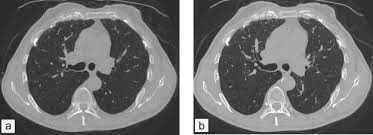

Une irm thoracique sans injection (figure 4) effectuée à titre complémentaire a mis en évidence cette même masse paravertébrale bilatérale hétérogène la myélofibrose pouvait aussi être discutée du fait de la haute densité osseuse au scanner, mais il n'y avait aucun argument biologique en ce sens. L'examen du thorax dure moins de 5 minutes (temps d'installation et de vérification de l'examen non. Le scanner est l'examen de base. Survient dans 18% des traumatismes de la rate. Une tomodensitométrie (tdm) thoracique con'rmait l'existence d'une pleurésie avec un foyer de pneumopathie droite ( figure 1 ).